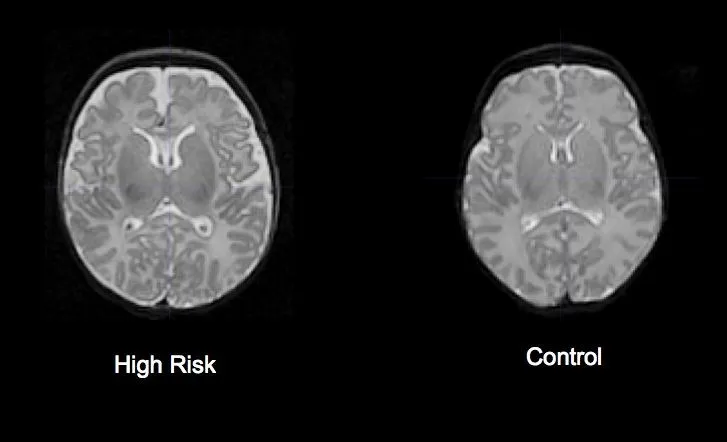

W badaniach naukowych, prowadzonych na dużych grupach pacjentów ze schizofrenią, obserwuje się pewne subtelne zmiany strukturalne w mózgu. Na przykład, często notuje się zmniejszoną objętość hipokampu (struktury kluczowej dla pamięci i emocji) oraz powiększenie komór bocznych mózgu. Są to jednak uśrednione wyniki, które pokazują statystycznie istotne różnice między grupą pacjentów a grupą kontrolną. Ważne jest, aby pamiętać, że te zmiany są niewielkie i występują w różnym stopniu u poszczególnych osób.

Niestety, na podstawie samego obrazu MRI nie jest dziś możliwe zdiagnozowanie schizofrenii u konkretnej osoby. Dlaczego? Ponieważ wspomniane zmiany nie są specyficzne wyłącznie dla schizofrenii – mogą występować również w innych chorobach neurologicznych, a nawet u zdrowych osób. Ich nasilenie jest zbyt zmienne, aby mogły stanowić samodzielne kryterium diagnostyczne w codziennej praktyce klinicznej. Diagnoza schizofrenii wciąż opiera się przede wszystkim na szczegółowym wywiadzie klinicznym i obserwacji objawów.

Standardowe badanie MRI nie jest narzędziem do bezpośredniego diagnozowania schizofrenii ani innych chorób psychicznych u pojedynczego pacjenta.